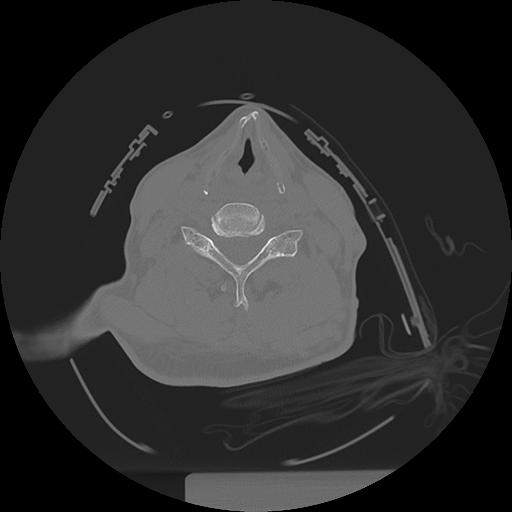

11 HUESO,,Axial,2.0,HUESO,,